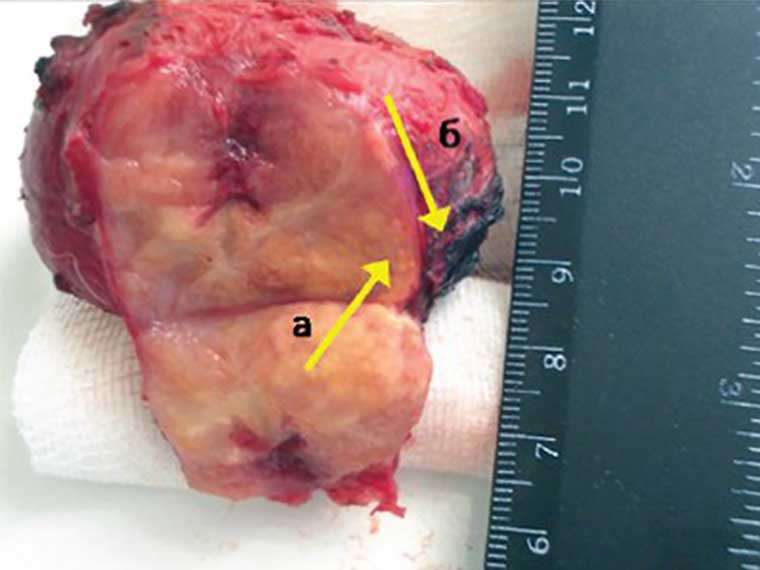

Prostat bezining masofaviy shishi (diametri 65 mm) Bundan tashqari, jinsiy zaiflik prostatit bilan kasallangan har bir erkakda 100% holatlarda sodir bo'ladi. Kimdadir ertaroq, kimdadir kechroq, biroq baribir sodir bo'ladi.

+ Rasmni ko'rsatishProstatitning juda xavfli kasallik ekanligini tushunishimiz kerak, chunki uning asosiy xavflaridan biri prostata bezi saratoniga aylanishidir. Bu esa, o'z navbatida, ko'pincha bemorni o'limga olib boradi. Nazoratsiz va davolanishsiz qolgan kasallik, ba'zida juda tez rivojlanib 1-2 yil ichida saraton paydo bo'lishiga olib keladi.